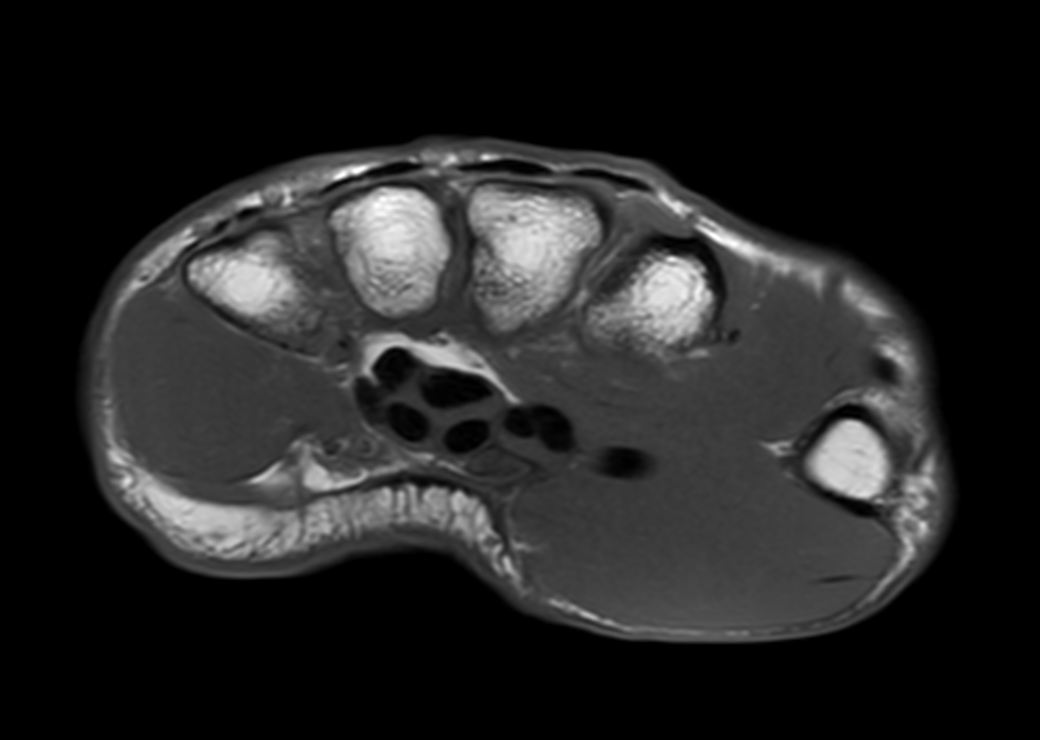

Axial T1w TSE

-

Axial T2w TSE